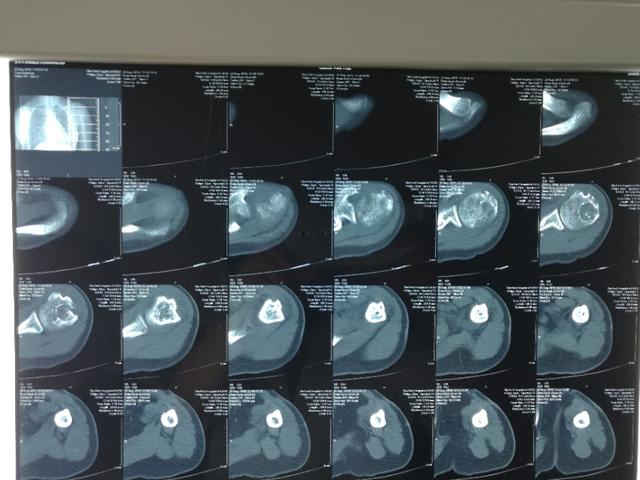

其他表现包括鼻腔、唾液腺组织和头颈部其他区域受累,溶骨性病变,肺结节,或者皮疹。X线等影像学可见占位性病变、溶骨性改变等!